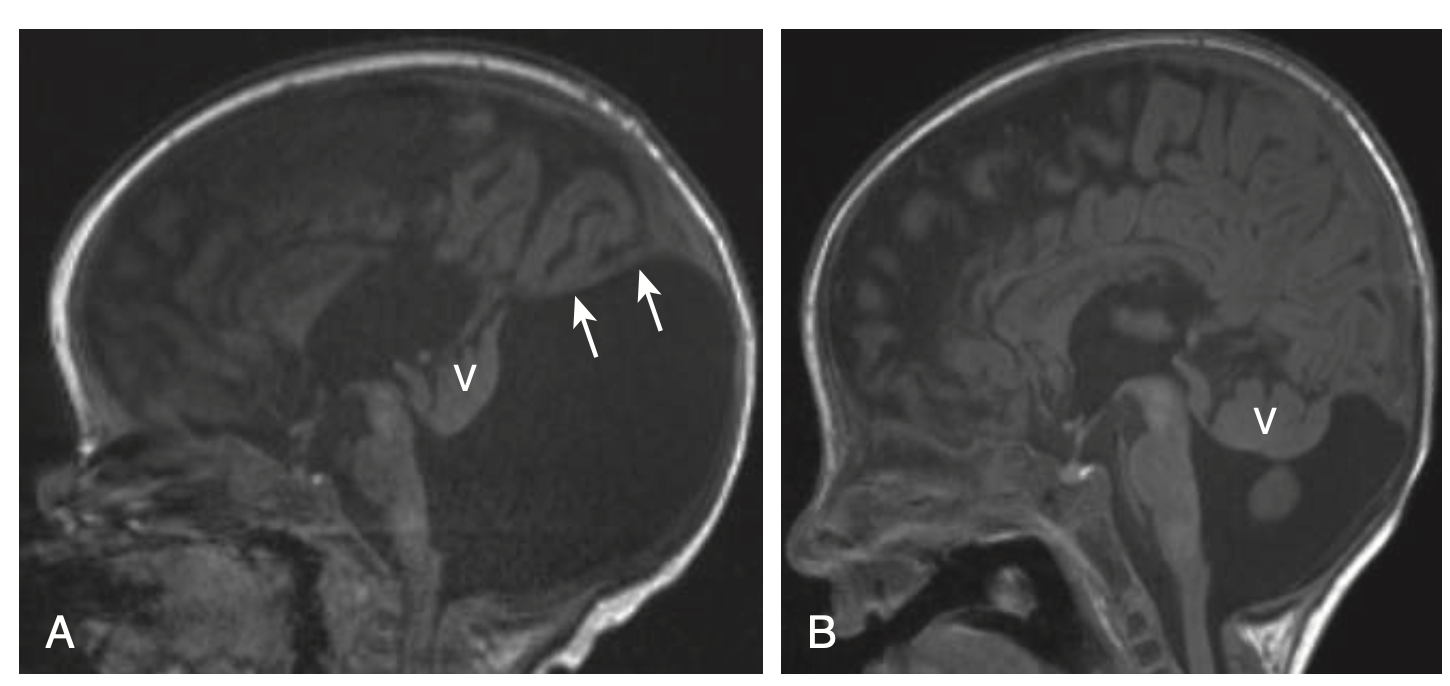

B. 뇌량 무형성 (Agenesis of the Corpus Callosum, ACC)

• 정의: 뇌량 (corpus callosum)의 형성 부전

• 임상 양상: 고립된 ACC는 무증상일 수 있으나, 다른 뇌 이상 동반 시 지적 장애 및 신경학적 이상 초래.

• 영상 특징 (MRI): 측뇌실이 평행하게 주행, 제3뇌실 위치 높음, colpocephaly (후두각 확장) 동반